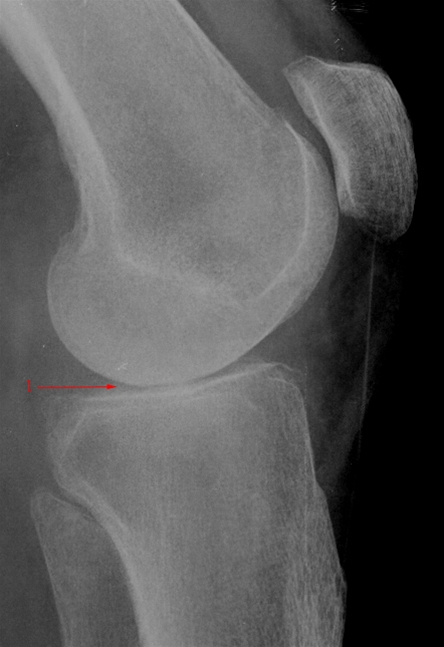

Gonartrose, moderat, side

Let reduceret bruskhøjde i knæleddet (1).